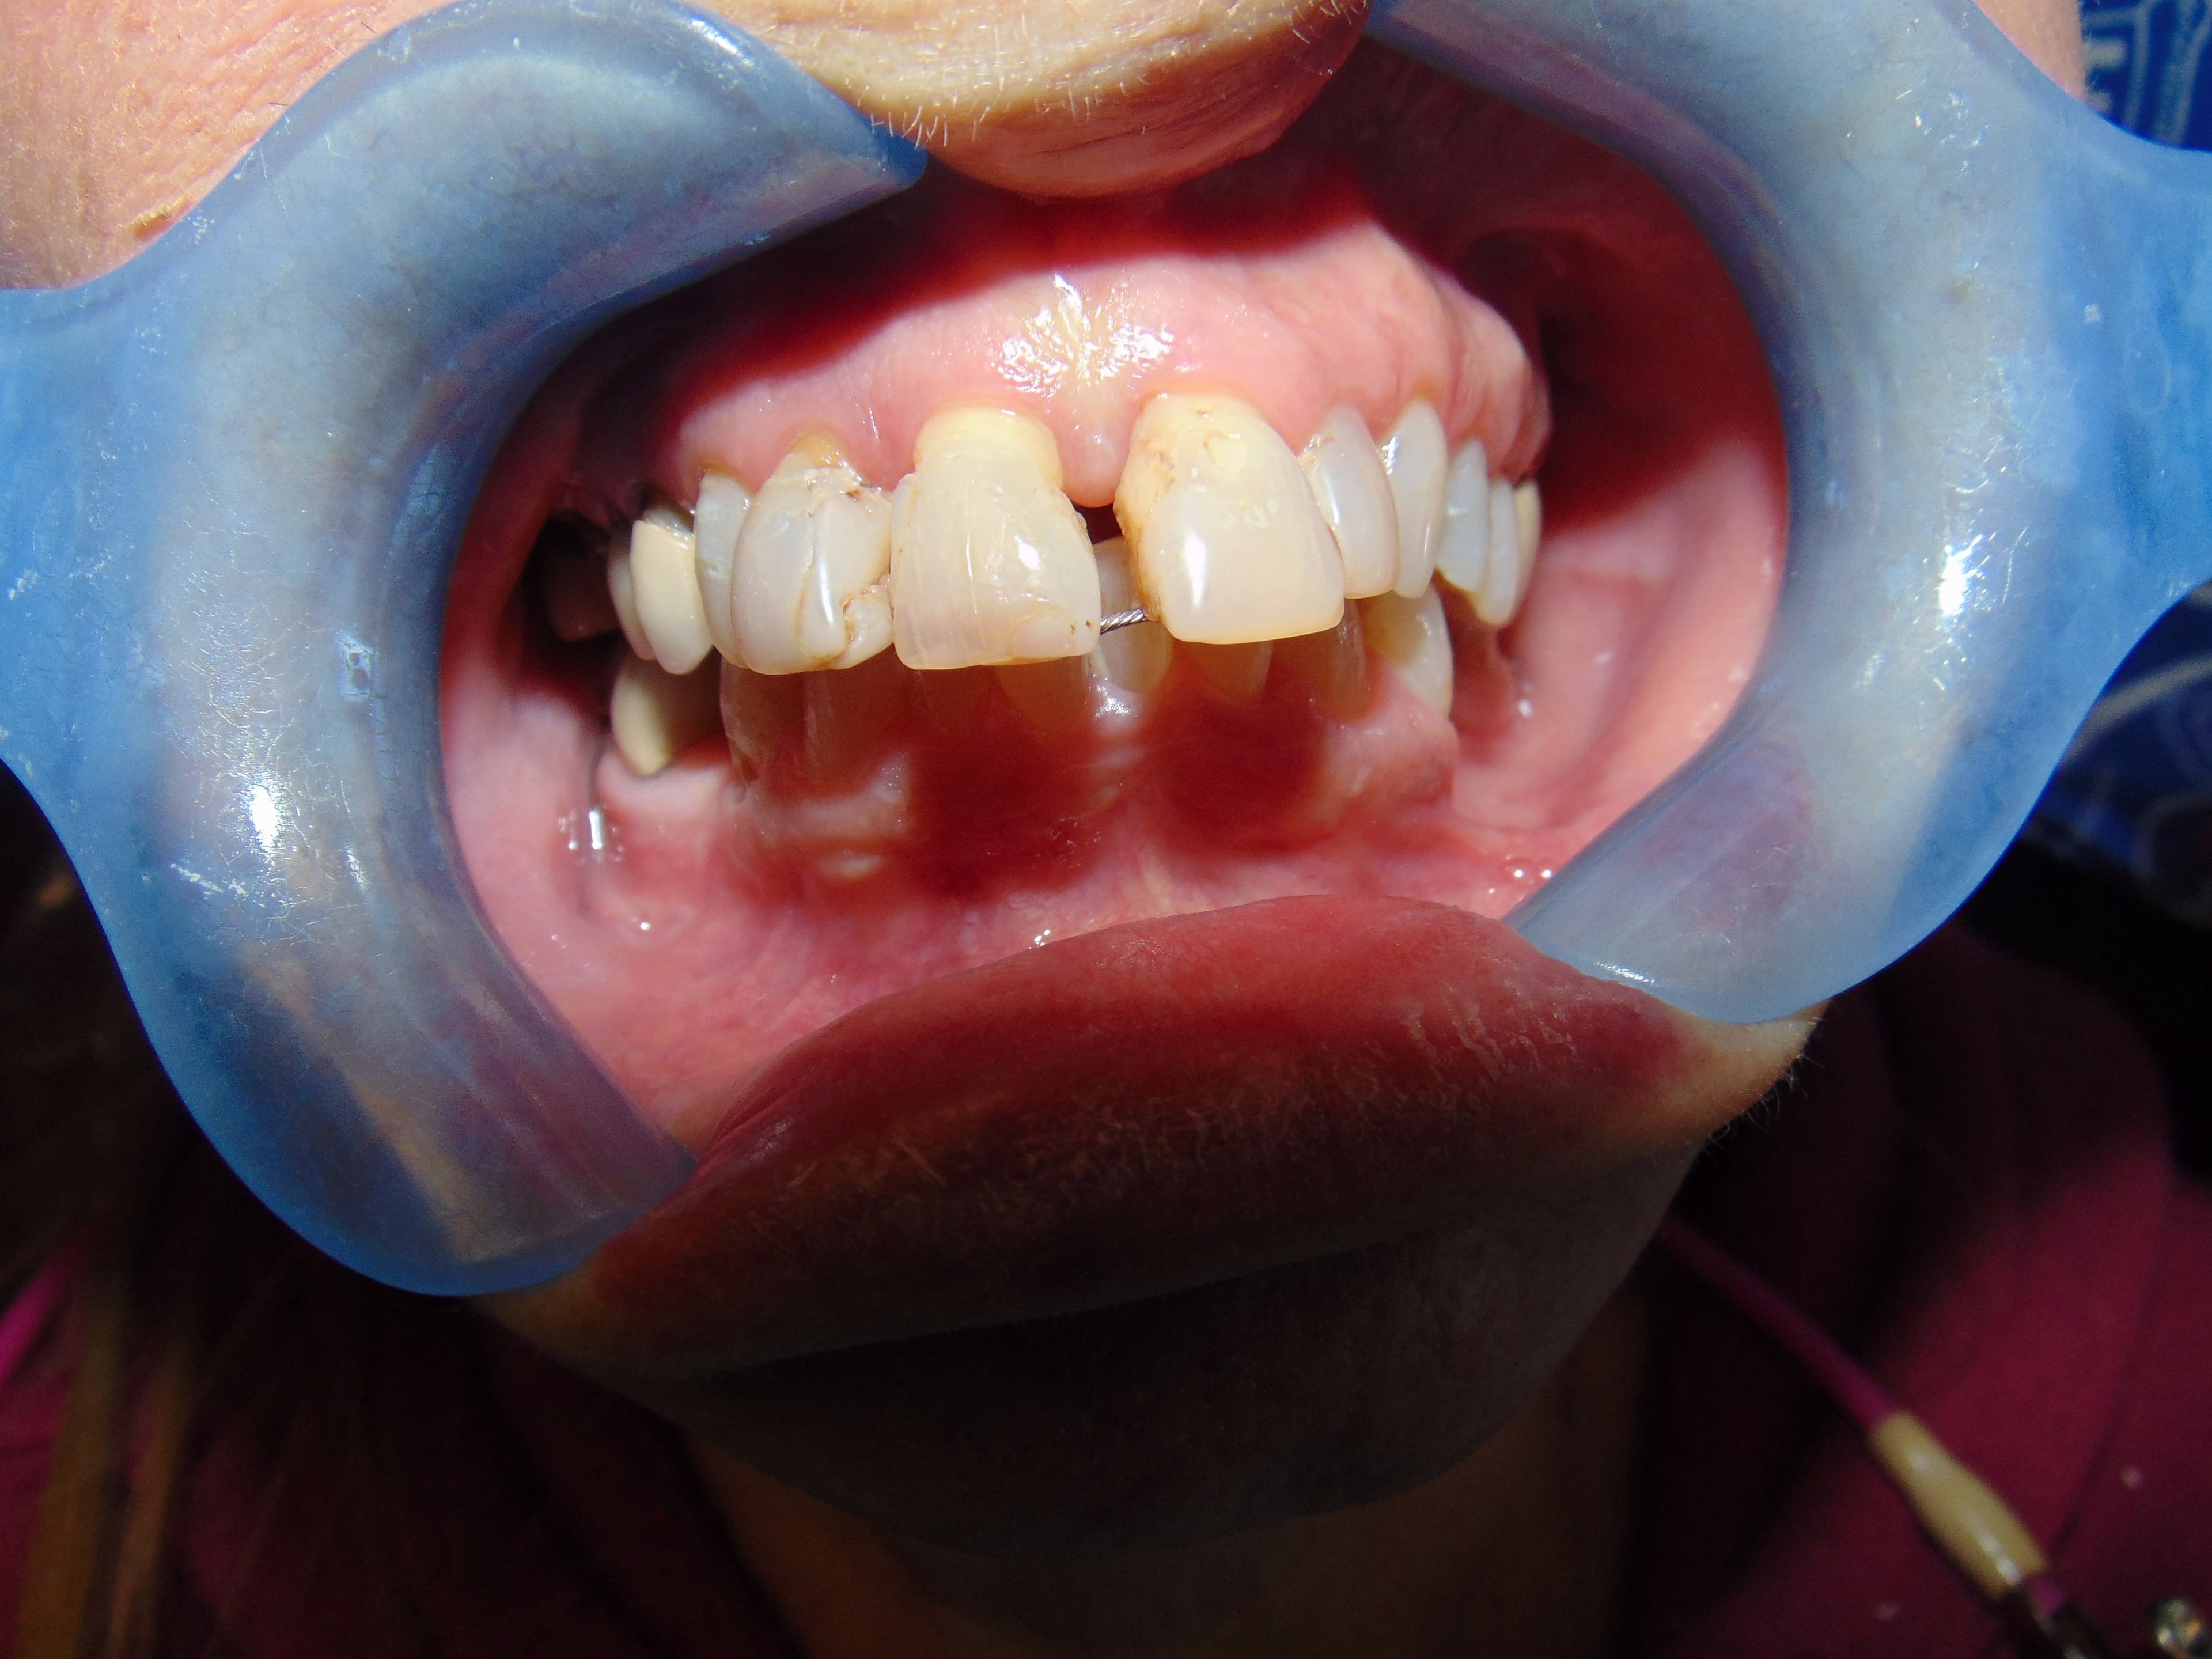

Case 12

58 yr old female with anterior splaying of upper teeth #7,8,9,& 10 due to periodontal bone loss resulting in total bite collapse and failure of wire splint and numerous bondings. Teeth #2,3,7,8,9,10 were extracted with selective bone grafting. Fabrication of transitional upper denture to be worn during the healing phase. Eight upper porcelain fused to metal crowns done to open occlusion approximately 3 mm to correct collapsed occlusion. Modifications were done to transitional prosthesis at each step to accommodate new crowns. Fabrication of upper valplast denture to complete restoration of upper dentition.